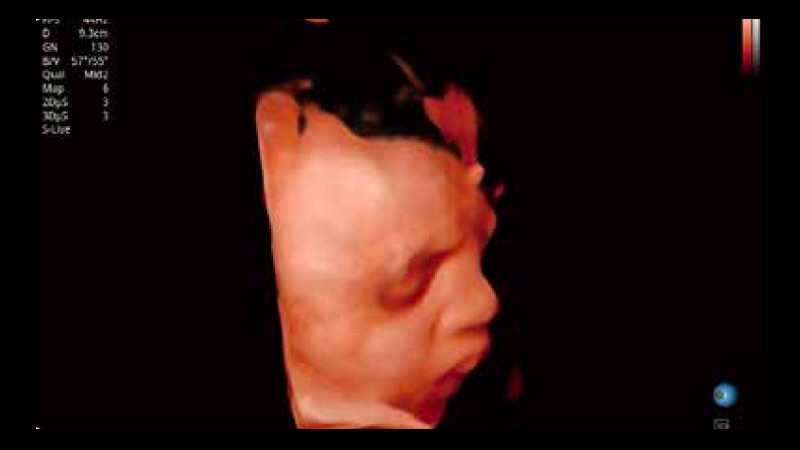

開立醫(yī)療通過不斷的技術(shù)創(chuàng)新,為大眾的生命健康提供持續(xù)關(guān)愛。P12 Plus采用全新一代超聲成像平臺,新平臺旨在將真實(shí)還原組織解剖結(jié)構(gòu)作為首要目標(biāo)。平臺采用全新集成化硬件模塊,搭載新一代芯片,系統(tǒng)性能得到大幅提升,為您的診斷提供了豐富的臨床信息。優(yōu)異的圖像表現(xiàn),豐富的探頭配置,全面的應(yīng)用功能,為您日常診斷提供了可靠的助手。